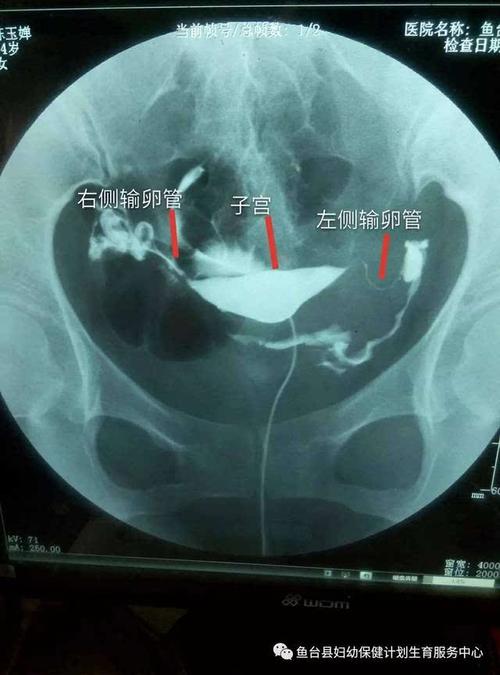

输卵管通水,就是利用造影器将药液管子插入女性的阴道,将造影剂流入女性的阴道内,从而收集到女人的身患“异物”的日子。输卵管通而不畅,可能还会伴随着阻塞,造成不孕,这个观点相信很多人都可以理解。那么输卵管的通水是不是真的对吗?

输卵管通水,先将造影剂注射在输卵管内,并将造影剂的管子固定在女性的管子的管子中间。之后,医生会将造影剂直接注入女性的阴道内,并通过相关医师的监视灯的照射,让造影剂能够注入到女性的体内,以达到事半功倍的效果。输卵管通而不畅,不仅会导致女性不孕,还会造成不孕。所以如果输卵管通水有问题,应该向专业的医生咨询之后是否可以做输卵管通而不影响输卵管手术的结果。